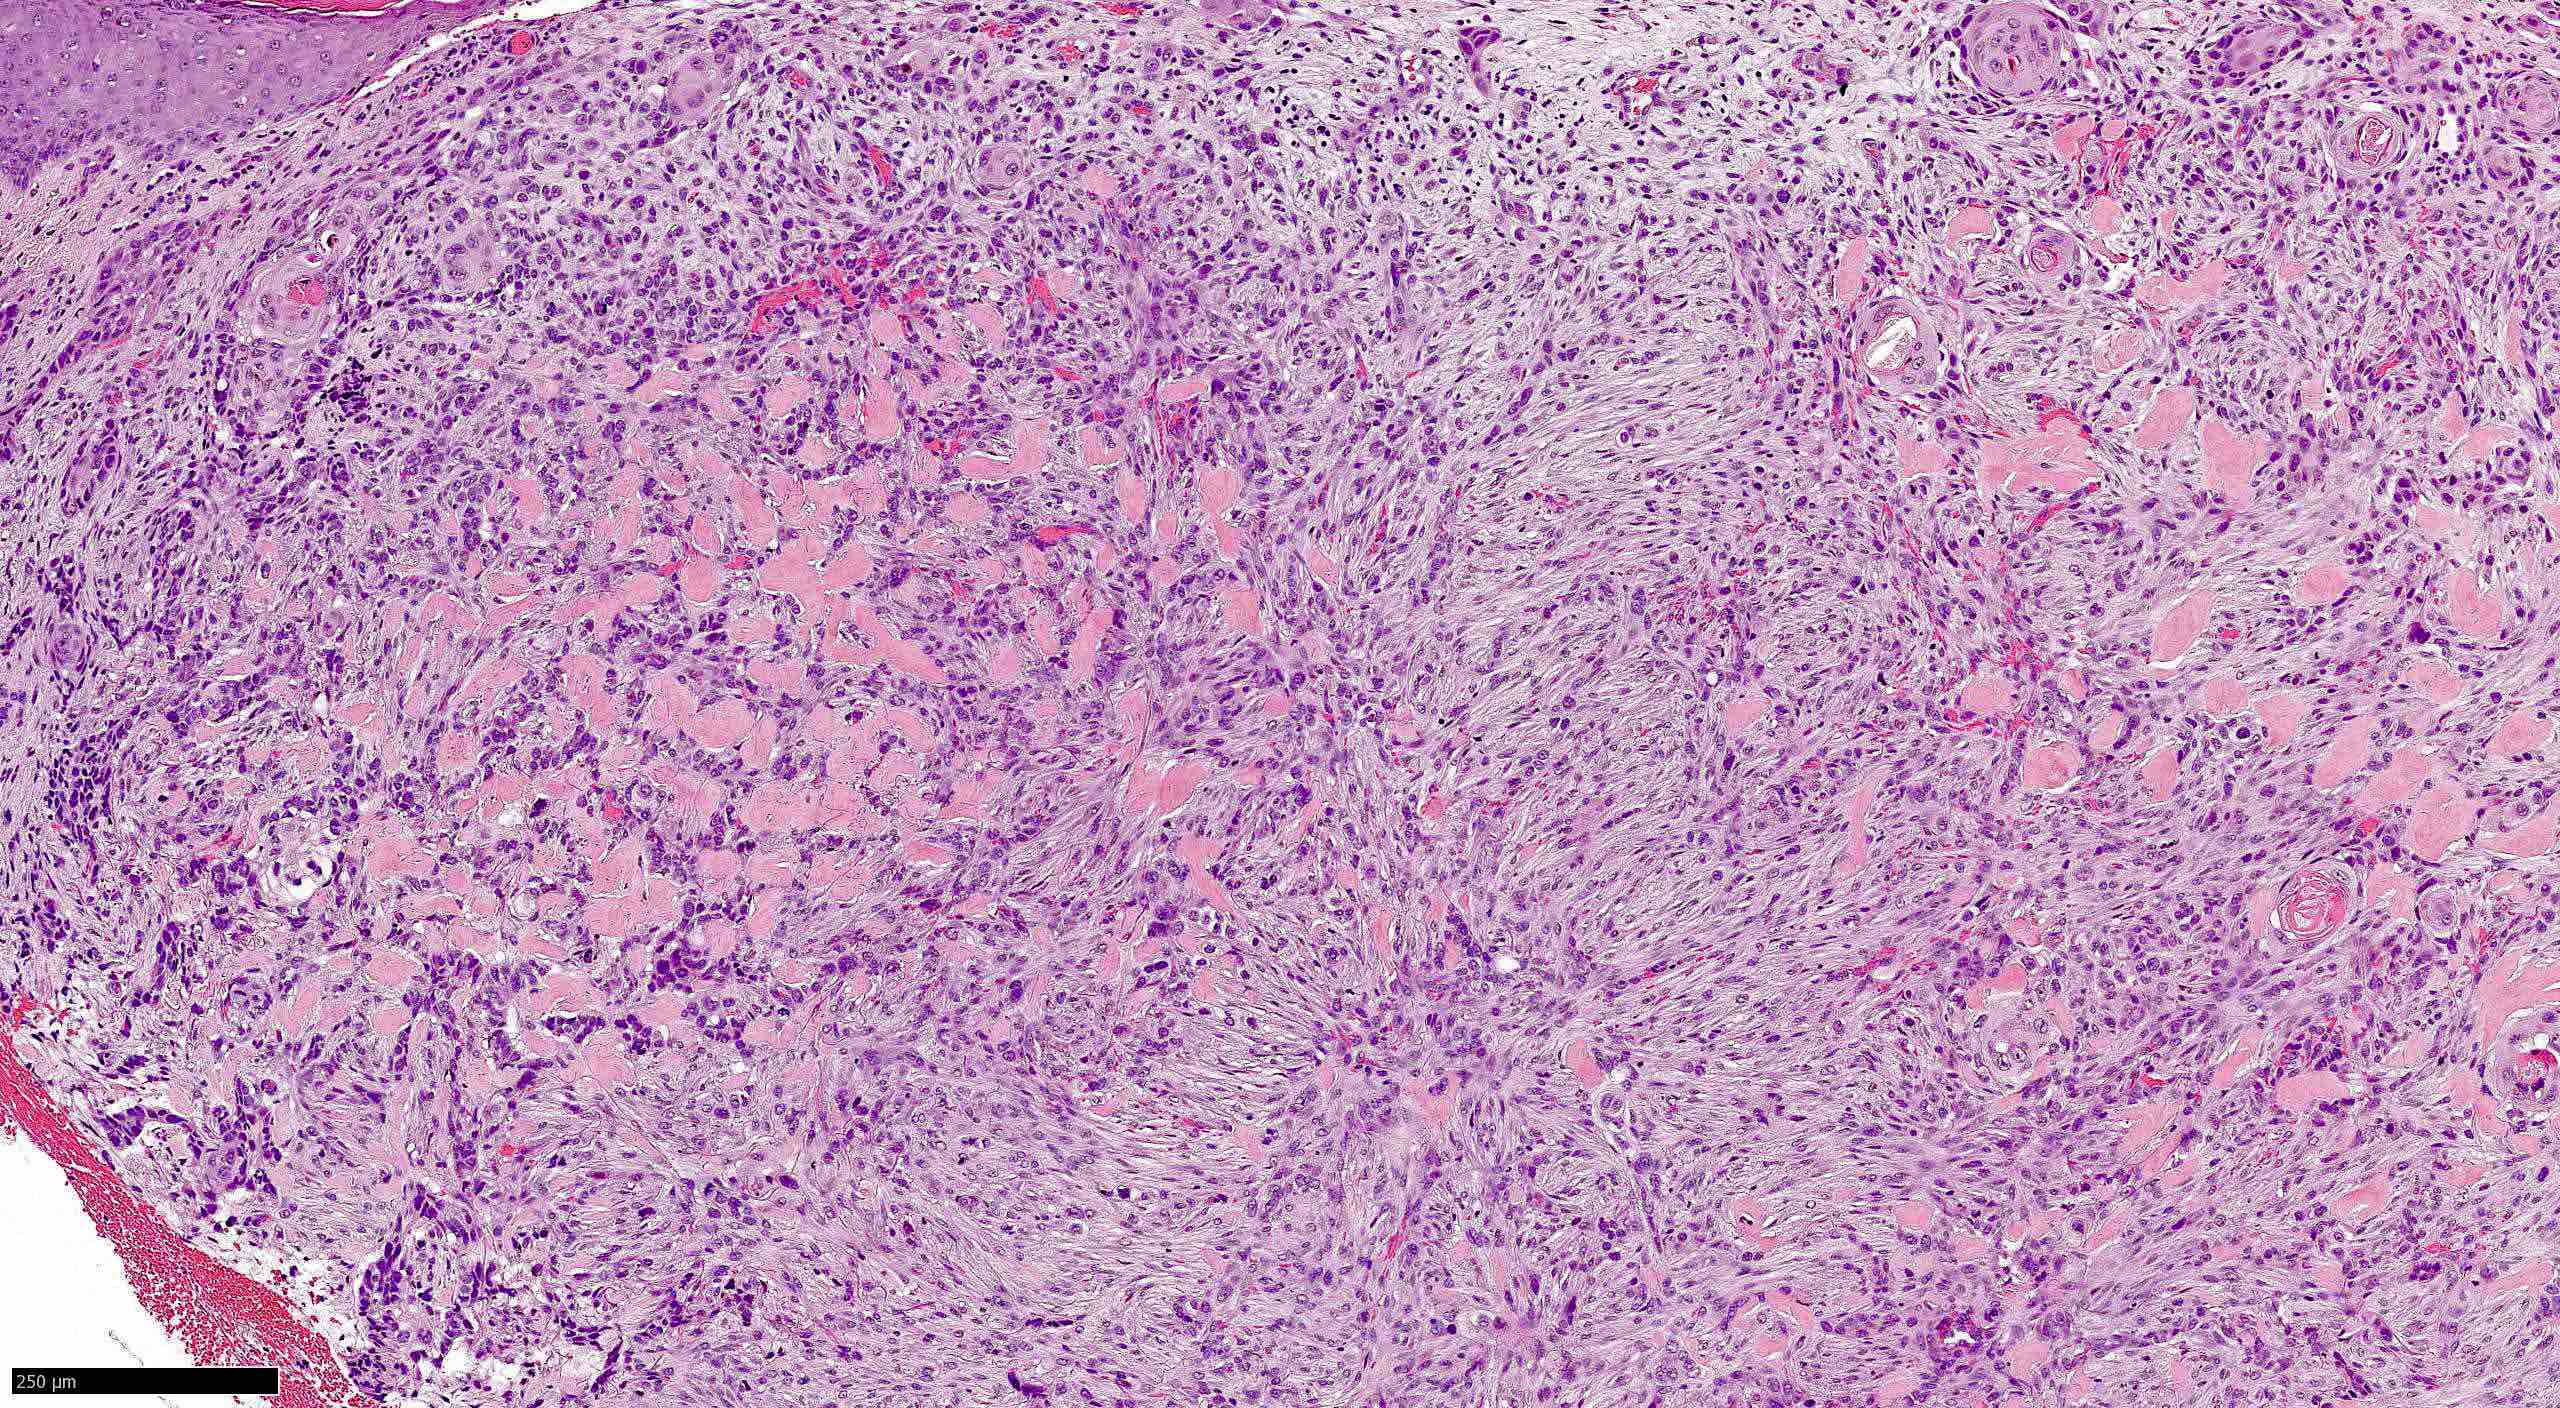

Common variants (Calonje: McKee's Pathology of the Skin, 5th Edition, 2019)

- Basosquamous (metatypical) BCC

- Biphasic tumor

- Foci of neoplastic squamous differentiation

Microscopic (histologic) images

Contributed by Antonina Kalmykova, M.D., Phillip H. McKee, M.D., Sate Hamza, M.D., Eduardo Calonje, M.D.,

Wayne Grayson, M.B.Ch.B., Ph.D., James Sampson, M.B.B.S., M.Sc. and Assia Bassarova, M.D., Ph.D.